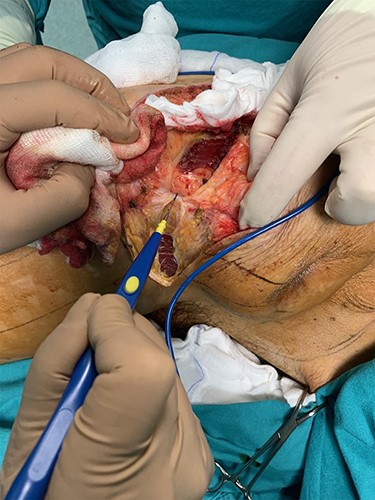

During the operation, surgeons exposed meticulously the liposarcoma that was utterly removed, and performed elective resection of the right iliac crest, the upper part of the sartorius muscle, part of the gluteus maximus muscle, and part of the muscles of the anterior abdominal wall in order to eliminate the potentiality of local recurrence of the liposarcoma (Figs. 5–7). The operation was uneventful, and two drainages were placed into the pelvic fossa. The drainages were removed the sixth postoperative day when the patient was finally discharged with instructions. The pathology report documented a well-differentiated liposarcoma of the right pelvic fossa. Finally, at the 6-month follow-up, the patient had no complication or recurrent lesions and oncologists declared that adjuvant therapy was not essential.

The resected liposarcoma with the adjacent tissues, for the elimination of the potentiality of local recurrence.